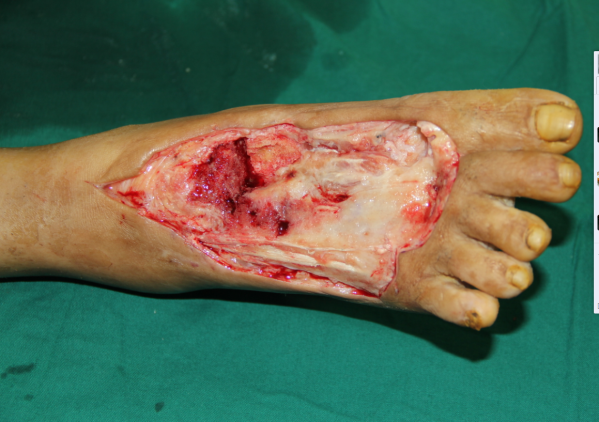

玉米机伤右足复合组织缺损,腓骨皮瓣修复,术后12天,伤口愈合良好,今日出院清创后

术中

跖趾关节成形